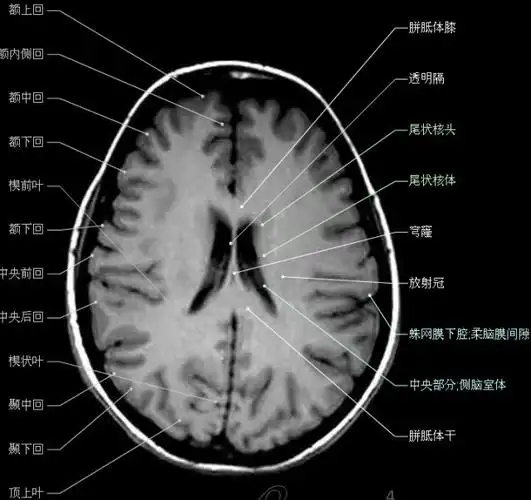

大集合颅脑轴向结构解剖图

影像回顾头颅基本断层解剖